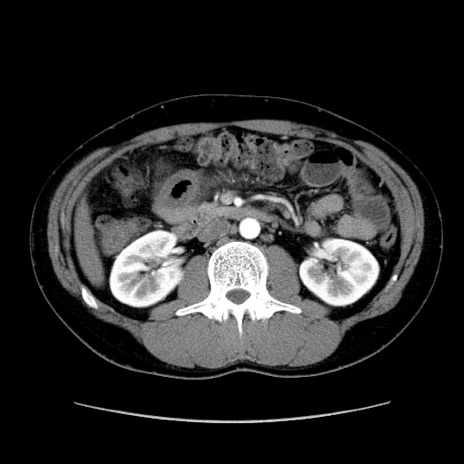

冠状断像

【症例】20歳代 男性

【主訴】心窩部痛

【現病歴】今朝より上腹部痛あり。一旦軽快していたが再度出現したため救急要請。昨日夕に白身の魚を含む刺身を食べた。

【身体所見】BP 136/89mmHg、HR 74/min、BT 37.0℃、腹部:膨満、軟、心窩部に圧痛あり。反跳痛なし、筋性防御なし、腸雑音やや亢進あり。

【データ】WBC 17700、CRP 0.48